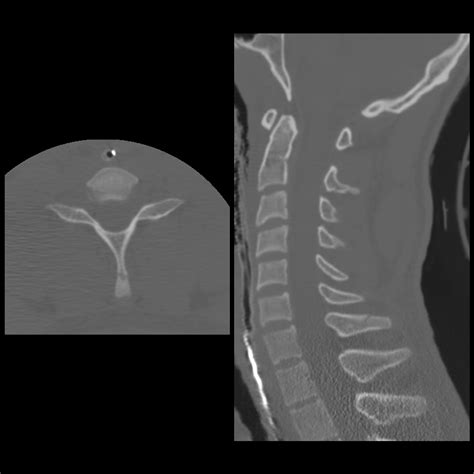

Diagnosis of Clay Shoveler's Fracture

Diagnosing a Clay Shoveler's Fracture involves a combination of physical examination and imaging tests. The diagnostic process typically includes:

• Imaging Tests:

• X-rays: To visualize the fracture and assess the extent of the injury.

• CT Scans: For a more detailed view of the bone structure and to rule out other injuries.